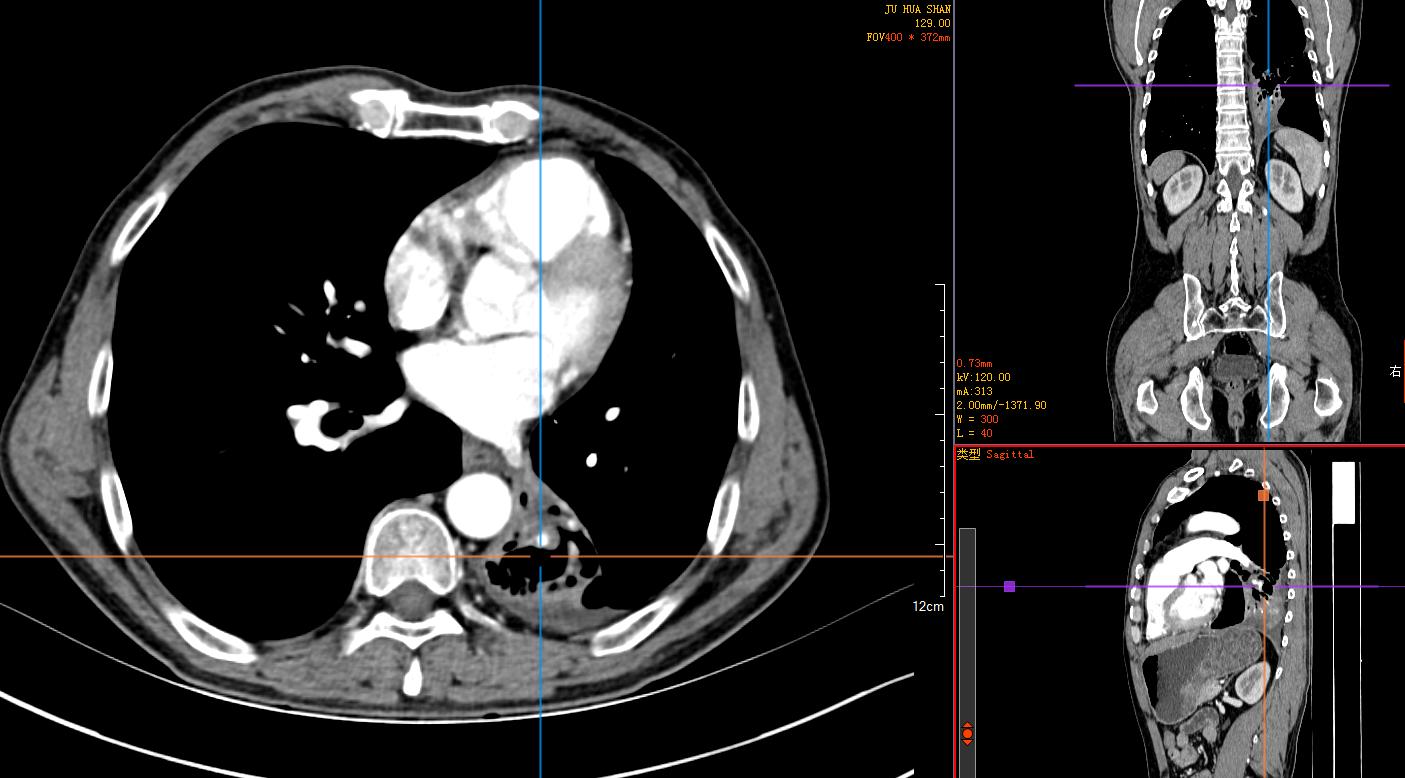

2)胸腹部平扫+增强CT示:左肺占位性肿块伴阻塞性肺不张,纵膈淋巴结肿大,建议穿刺活检。左肺动脉分支动脉瘤;右肾小错构瘤可能;双侧股骨颈小滑膜疝。